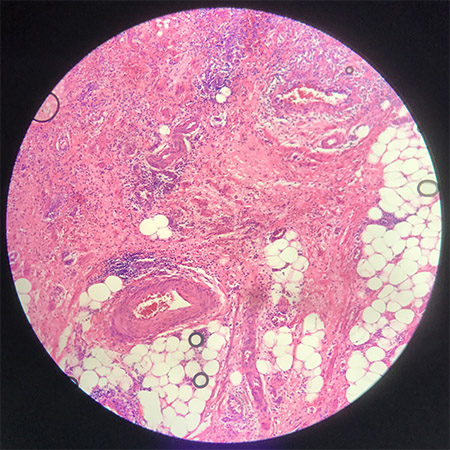

1分钟后

镜下看到的气泡能原地自溶,对使用技术来说,不用担心封出气泡,对于诊断来说看着顺眼不影响看片心情,科室存档不用担心气泡地方褪色。